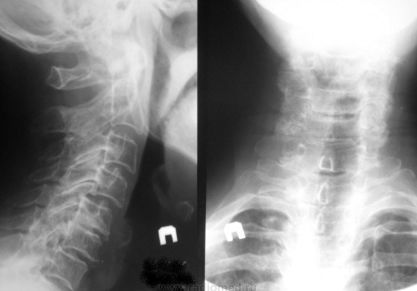

Остеохондроз — симптомы, лечение, признаки, полное описание заболевания

Почему возникает остеохондроз: причины и провоцирующие факторы. Механизм развития. Симптомы болезни и лечение остеохондроза позвоночника.